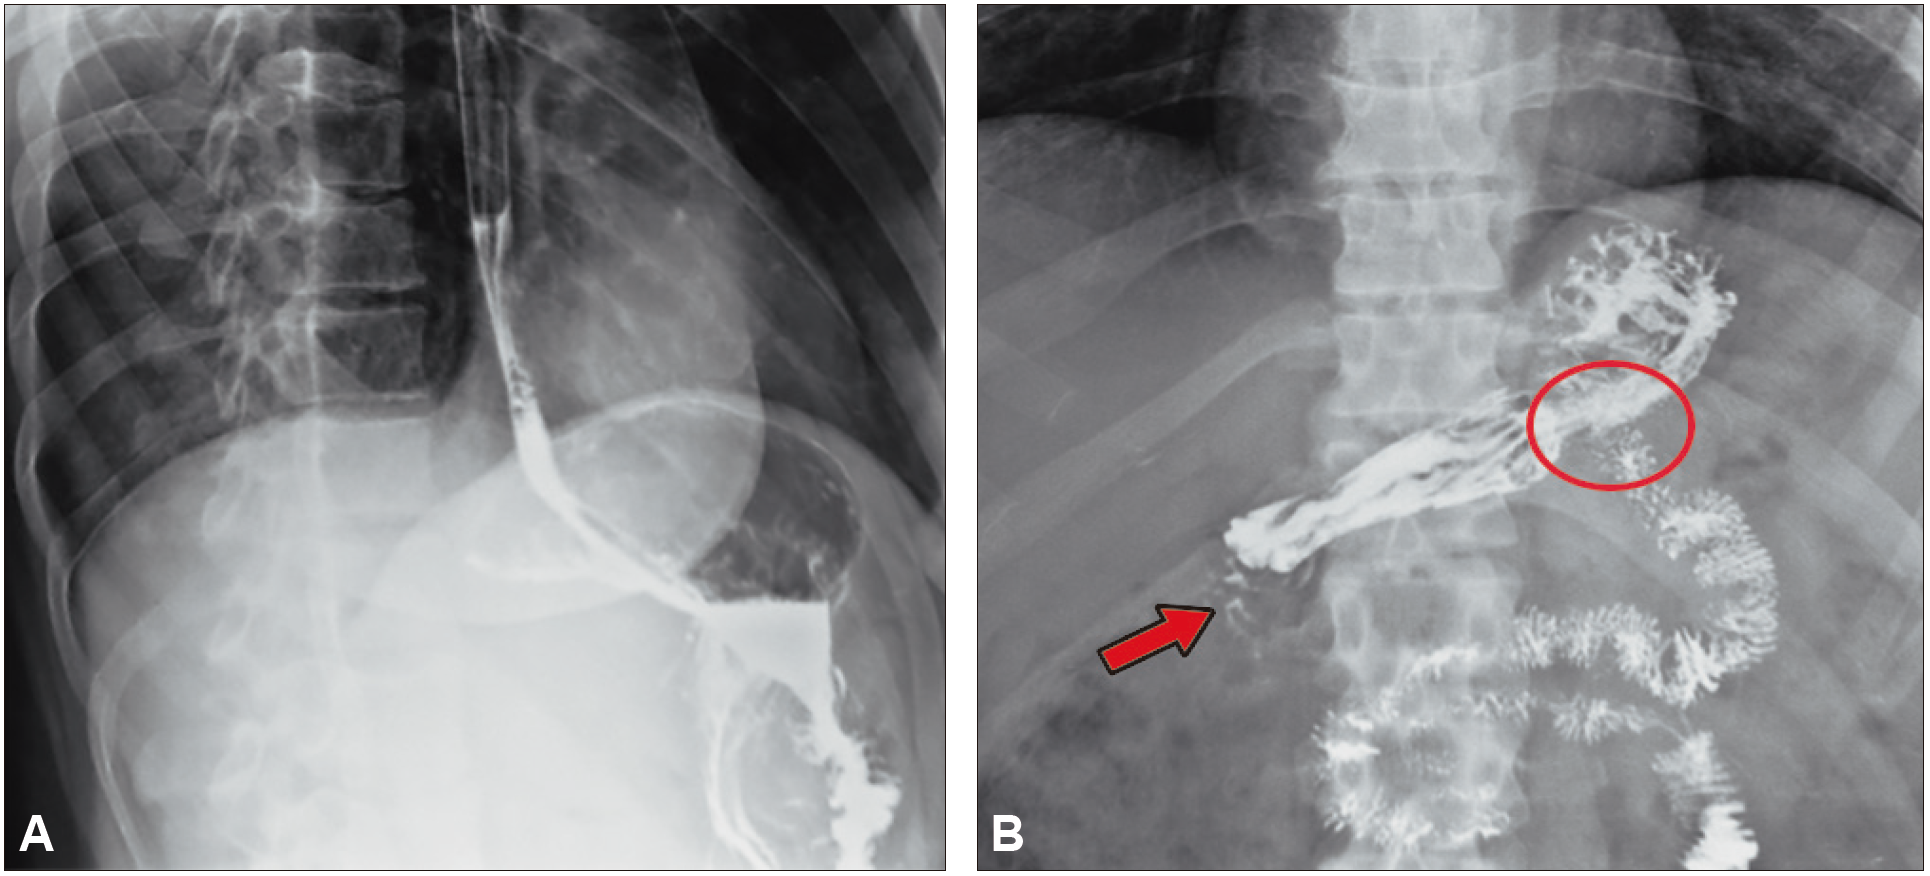

Paciente femenina de 42 años con antecedente quirúrgico de derivación gástrica en Y de Roux por vía laparoscópica realizada hace 12 meses, consulta al Servicio de Gastroenterología por presentar epigastralgia. Se le solicita, en primera instancia, un estudio seriado esófago gastroduodenal con doble contraste.

Figura 1. Estudio baritado del tubo digestivo alto. Proyecciones

obtenidas luego de la administración de contraste baritado

A: En posición decúbito lateral

izquierdo se evidencia adecuado pasaje de contraste desde el esófago hacia la cámara gástrica. B: En

posición decúbito supino se observan cambios morfológicos posquirúrgicos relacionados con anastomosis

gastrointestinal (círculo rojo) y filtración del medio de contraste distal al remanente gástrico (flecha

roja).